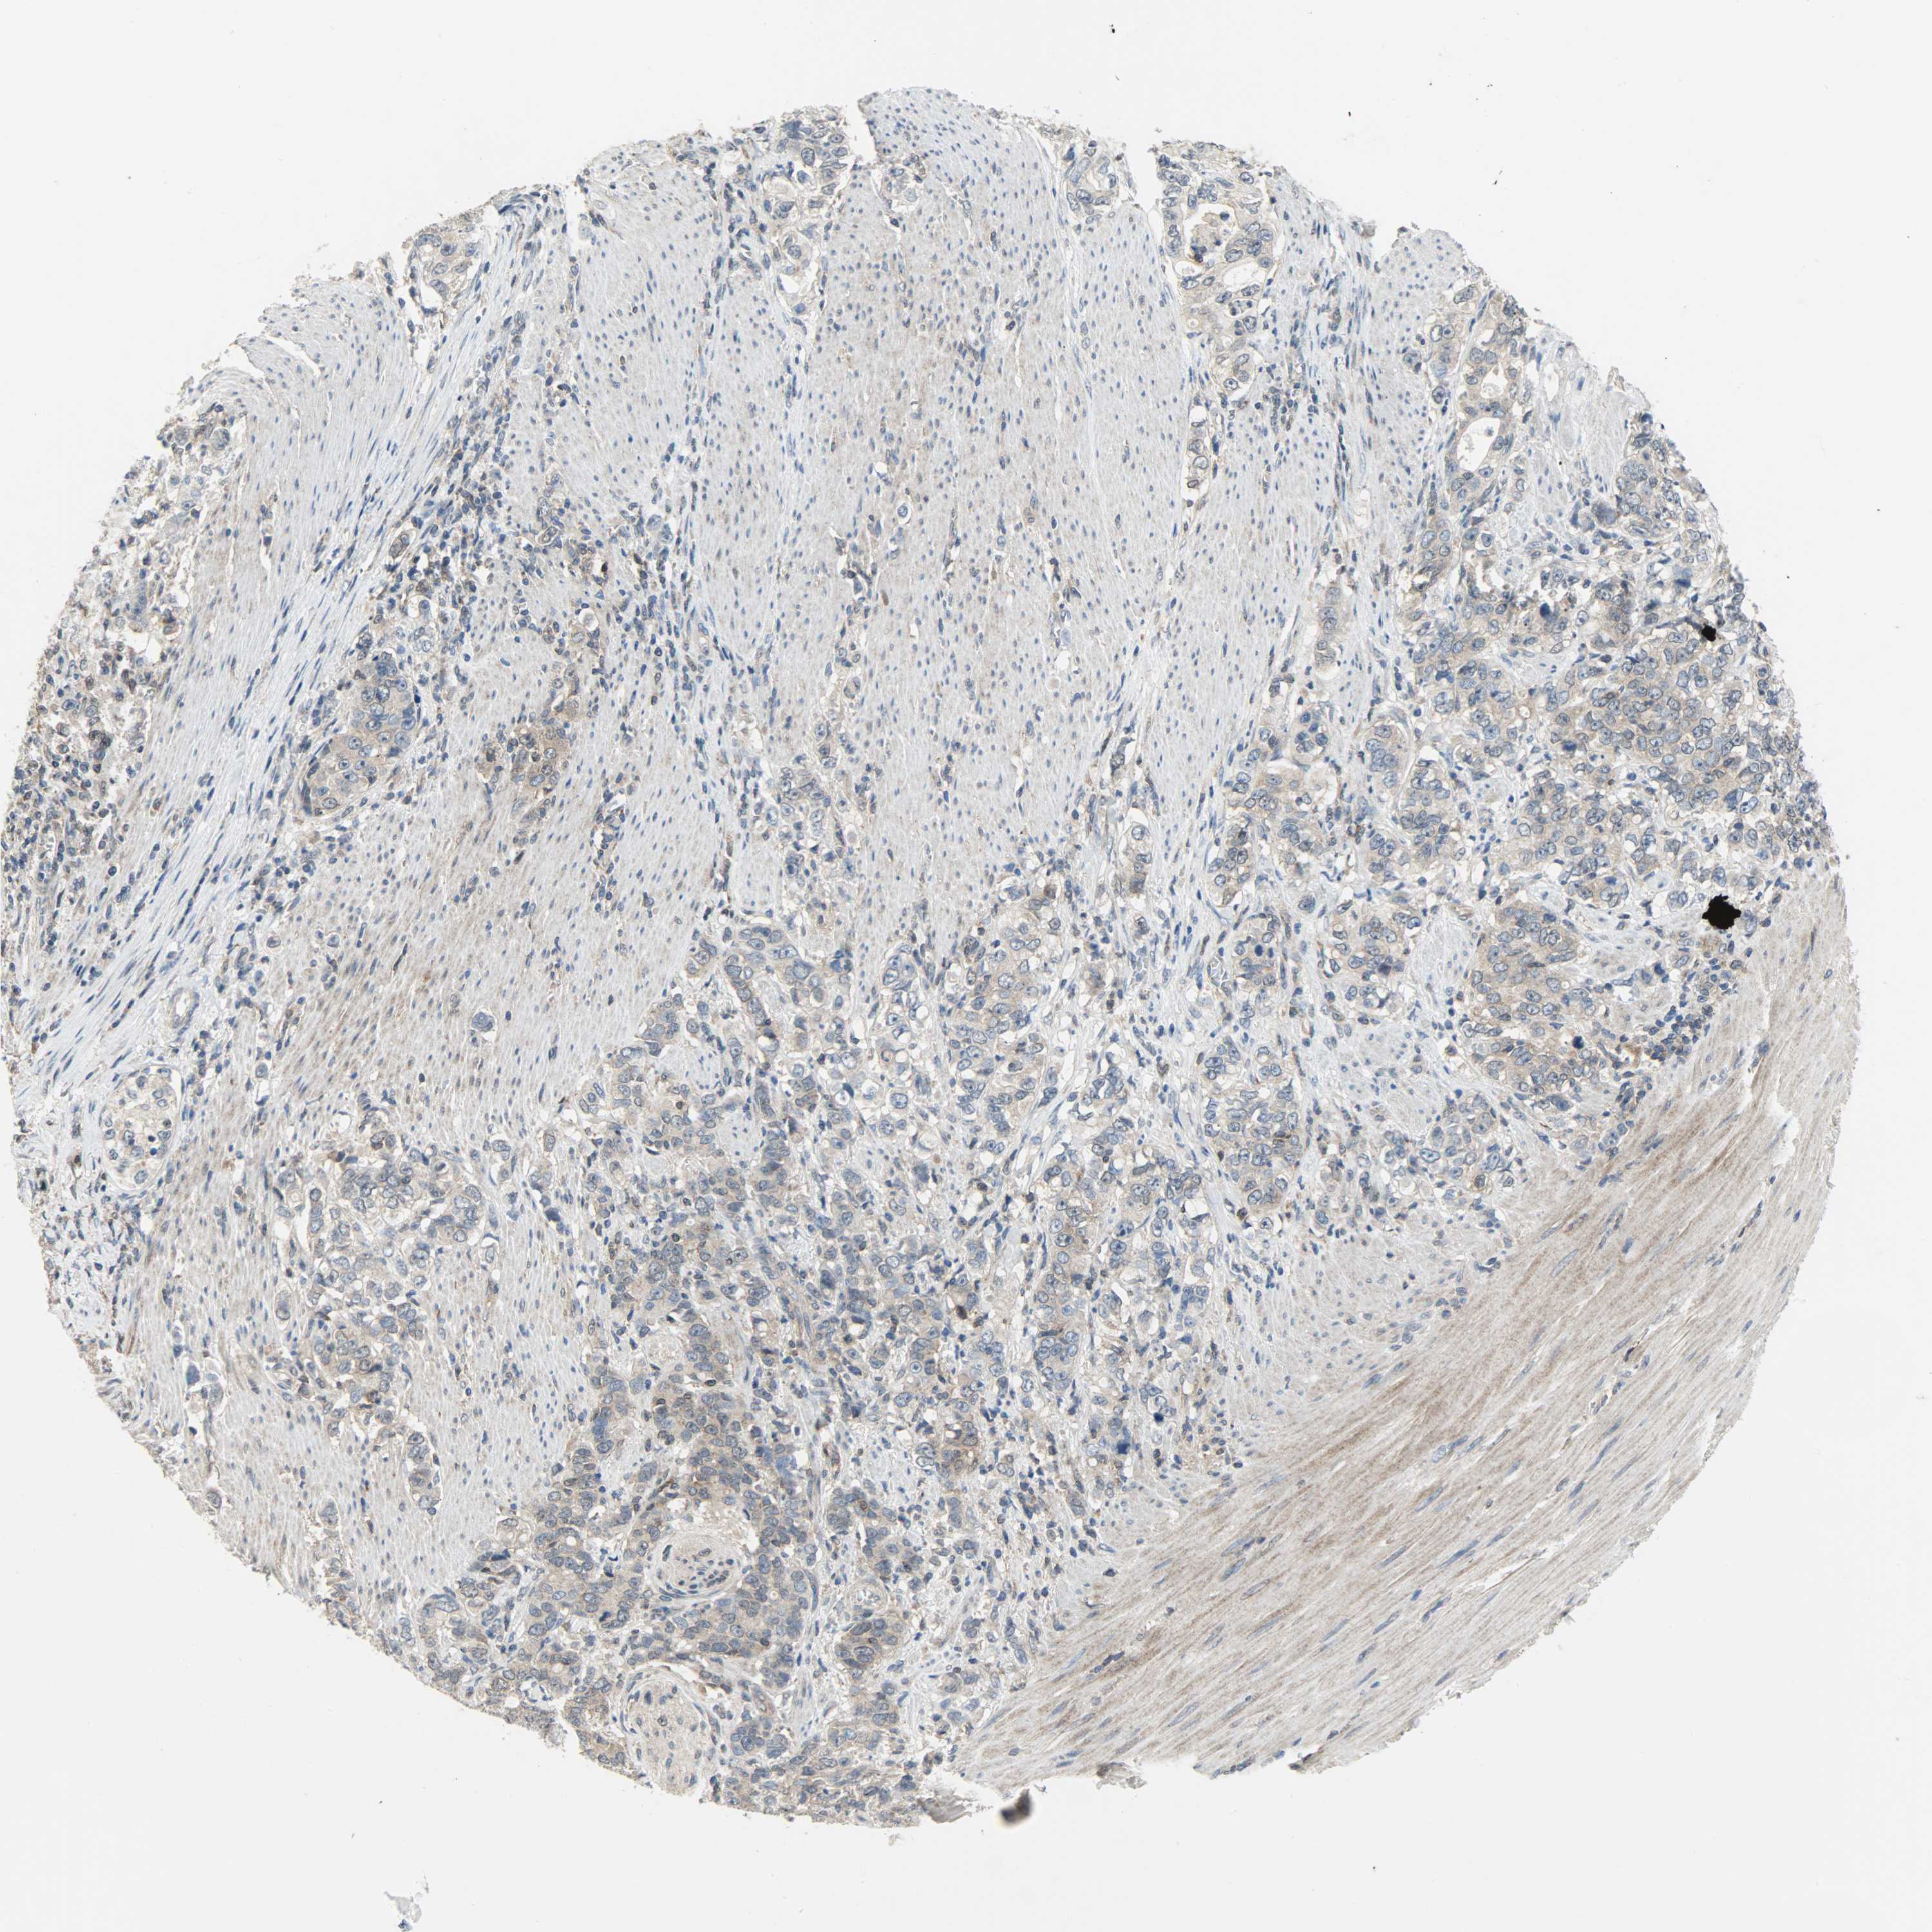

STOMACH CANCER - Protein expressioni

A mouse-over function shows sample information and annotation data. Click on an image to view it in a full screen mode. Samples can be filtered based on level of antibody staining by selecting one or several of the following categories: high, medium, low and not detected. The assay and annotation is described here.

Antibody stainingi

Antibody staining in the annotated cell types in the current human tissue is reported as not detected, low, medium, or high, based on conventional immunohistochemistry profiling in selected tissues. This score is based on the combination of the staining intensity and fraction of stained cells.

Each image is clickable and will lead to virtual microscopy that enables deeper exploration of all samples and also displays staining intensity scores, fraction scores and subcellular localization as well as patient and tissue information for each sample.

Antibody HPA005673

Antibody CAB004566

Staining

High

Medium

Low

Not detected

Intensity

Strong

Moderate

Weak

Negative

Quantity

>75%

75%-25%

<25%

None

Location

Nuclear

Cytoplasmic/membranous

Cytoplasmic/membranous,nuclear

Adenocarcinoma, NOS

Adenocarcinoma, High grade